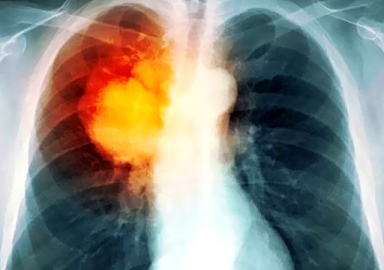

Akciğer kanserli hastalarda toplardamar tıkanıklıklarının çok rastlandığına değinen uzmanlar bacaklarda şişme ve ağrı gibi şikayetlerin dikkate alınması gerektiğine vurgu yapıyor. Derin ven trombozu denilen bu durum zamanında önlem alınmazsa akciğer embolisine neden olup hayati sonuçlar doğurabiliyor. Konu ile ilgili bilgi veren Göğüs Cerrahisi Uzmanı Doç.Dr. Özkan Demirhan, "Kanserli hastalarda toplardamar tıkanıklıklarına çok sık rastlıyoruz. Kanser hastalarının kanındaki yapısal bozukluklar, pıhtılaşmaya olan eğilimlerden dolayı toplardamarlarda pıhtılaşmadan dolayı sıkıntılar yaşanabiliyor" dedi.

Bacak şişmesinden dolayı başvuran hastada yapılan ileri tetkiklerde akciğer kanseri tanısı konulabiliyor. Akciğer kanseri teşhisi konulmamış bazı hastalarda toplardamar tıkanıklıklarından dolayı yapılan ileri tetkiklerde akciğer kanseri teşhisinin de konulabildiğine değinen Doç.Dr. ÖzkanDemirhan, "Özellikle akciğer kanserli hastalarda toplardamar tıkanıklığı akciğer kanserinin bir işareti olabiliyor. Bu nedenle bacaklardaki şikayetleri atlamamak gerekir. Derin ven trombozu dediğimiz bacaktaki toplardamar tıkanıklığından dolayı bacaklarda şişme ve ağrı meydana geliyor. Bu bize direkt kansere bağlı bir pıhtılaşma bozukluğunu gösterebiliyor" ifadelerini kullandı.

Hasta kanserden kaybedilmese bile akciğer embolisinden kaybedilebilir bu yüzden mutlaka önlem almak gerekir. Bu durumun ihmal edilmesi durumda hayati sonuçlar doğurabileceğine değinen Özkan Demirhan, "Bazen buradaki pıhtıların akciğere gitmesi sonucu akciğer embolisi dediğimiz çok ciddi durumlara da yol açabiliyor. Bu yüzden tedbir erken alınmalı. Akciğer kanserinin teşhisi konmuş hastalar ameliyat esnasında, ameliyat sonrası hatta ameliyat olamayacak hastalar da dahi toplardamar tıkanıklıkları medyana gelmekte. Hastalar kanserden kaybedilmese bile toplardamar pıhtılaşmasından kaybedebiliyor. Bu pıhtılaşmalar mutlaka hekim kontrolünde medikal şekilde ediliyor. Tedavi seçenekleri arasında başta kan sulandırıcılar olmak üzere ağızdan alınan ilaçlar, cilde yapılan iğne, damardan verilen kan sulandırıcılarla ve antiembolik çoraplarda kullanılmakta. Nadir durumlarda ana toplardamara filtre konuluyor" bilgilerini verdi.